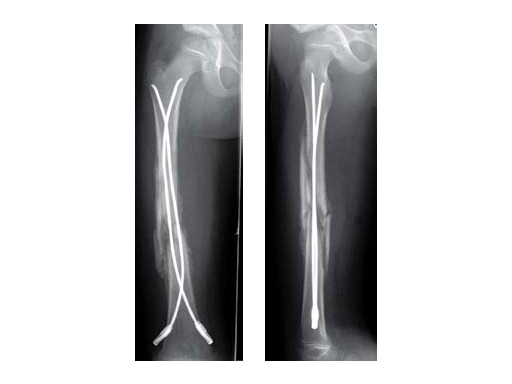

Case of a 8-year old boy with a closed lower leg fracture after football game. Control at 4 and 8 weeks after fractrure.

8-year-old boy.

Case provided by Steffen Berger and Theddy F Slongo, Bern, CH